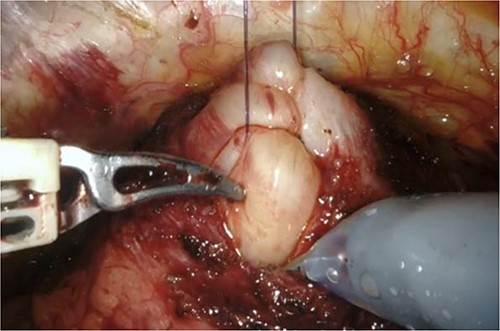

RARP was performed without preoperative hormone therapy. All steps of the RARP procedure were based on a previously established method described by Patel et al. [5], in which all procedures were performed via the transperitoneal approach with a six-port technique. In our patient, we performed conventional RARP. In cases with middle-lobe hypertrophy, prostate dissection around the bladder neck is an important feature. In this procedure, the border between the bladder neck and prostate is dissected using electrocoagulation, and when the middle lobe of the prostate is exposed, it is punctured using a 25-cm, 26-mm, 3–0 monofilament needle and lifted using the fourth arm several times (Fig. 2). The manual procedure, involving pulling in various directions and re-puncturing when the middle lobe is exposed, is repeated until the middle lobe is completely exposed. This reveals the bladder trigone and ureteral orifice and allows identification of the appropriate resection line. At this point of the dissection, the prostate is dissected, the dorsal seminal vesicle is penetrated, and finally, the Denonvilliers fascia is dissected (Fig. 3). Surgery was completed without additional suturing in the bladder neck side. The console time was 2 h 9 min, and the anesthesia time was 3 h 40 min. Bleeding volume was 28.5 ml, including urine volume. The weight of the removed prostate was 70 g. The pathological features were as follows: tumor size 10 × 5 mm (largest tumor layer); Gleason score 4 + 3 = 7; and adenocarcinoma pT2c, ly0, v0, pn0, sv0, EPE0, and RM0. Postoperatively, there were no anastomotic leaks, and no serious complications, categorized as grade 2 based on the Clavien–Dindo classification v2.0, developed.

Grasping of the thread with the fourth arm followed by lifting.